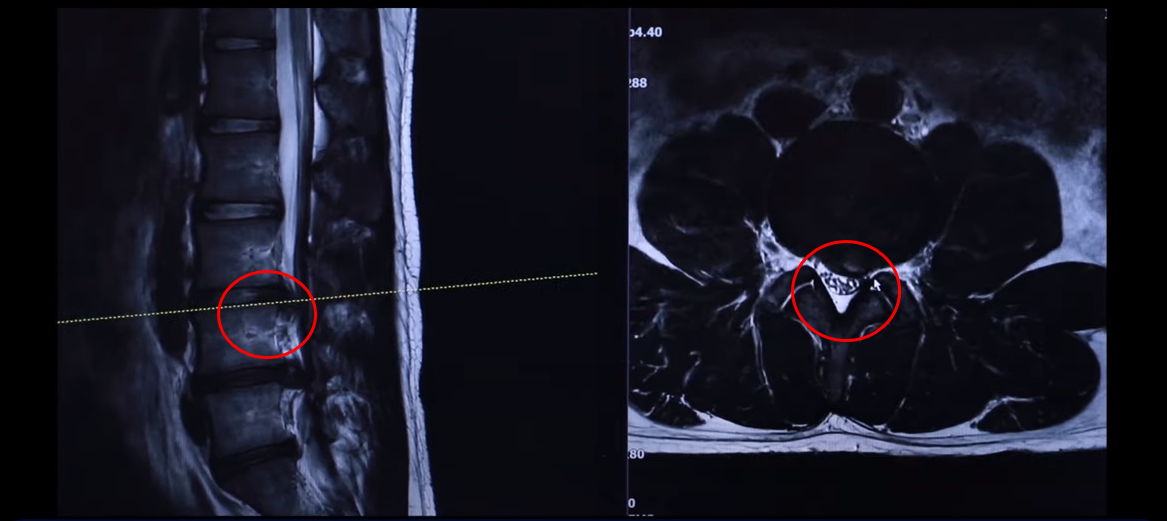

단면을 한번 보도록 하겠습니다. 여기를 잘라서 본 단면인데요. 왼쪽으로 많이 밀려 나와 있죠? 이 한마디만 해도 파열돼서 상당히 많이 밀려 나온 겁니다. 왼쪽 다리가 저리고 아플 수 있습니다.

그 다음 마디 4번, 5번 보시면 보시다시피 아예 신경이 거의 보이지 않을 정도로 많이 밀려나왔습니다. 이렇게 심하게 파열된 경우를 보는 건 참 드뭅니다. 거의 신경이 보이지 않을 정도로, 오른쪽에 약간 하얀 부분이 남아 있습니다. 그래서 이 환자분 증상이 왼쪽 다리 증상입니다.

저희가 여러분한테 누누이 말씀 드리지만 터진 걸 가지고 수술하는 게 아닙니다. 증상이 중요합니다. 어떤 경우에는 무조건 수술을 해야 되느냐, 특히 4,5번 같으면 신경 다발이 아예 다 눌려 버리지 않았습니까? 이렇게 눌리면 대소변 장애나 다리에 마비가 올 수 있습니다. 특히 대소변 장애와 다리 마비를 동반하는 걸 마비증후군이라고 하는데 대소변 장애, 특히 대변과 소변이 아예 컨트롤이 안 된다, 그러니까 참으려고 해도 참을 수가 없이 새버린다 하면 그건 무조건 수술을 하셔야 됩니다. 그런데 대소변 장애가 심하지 않다, 그러니까 내가 대변이나 소변이 마려운지 잘 모르겠다, 그 정도는 저희가 수술하지 않고 치료하고 있습니다. 마찬가지로 발목에 마비가 생겼다. 그래서 족하수가 생겼다, 풋드랍이 생겼다, 뒤꿈치로 설 수가 없다 아니면 까치발을 할 수 없다, 이런 마비 증상은 저희가 치료를 하고 있습니다.